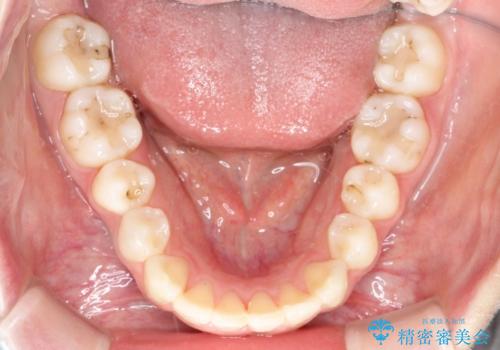

【インビザライン】前歯のガタガタをなおしたい。

- 前歯の凸凹を主訴に来院されました。

インビザラインにて奥歯の遠心移動を行いながら、前歯のガタガタを改善することができました。